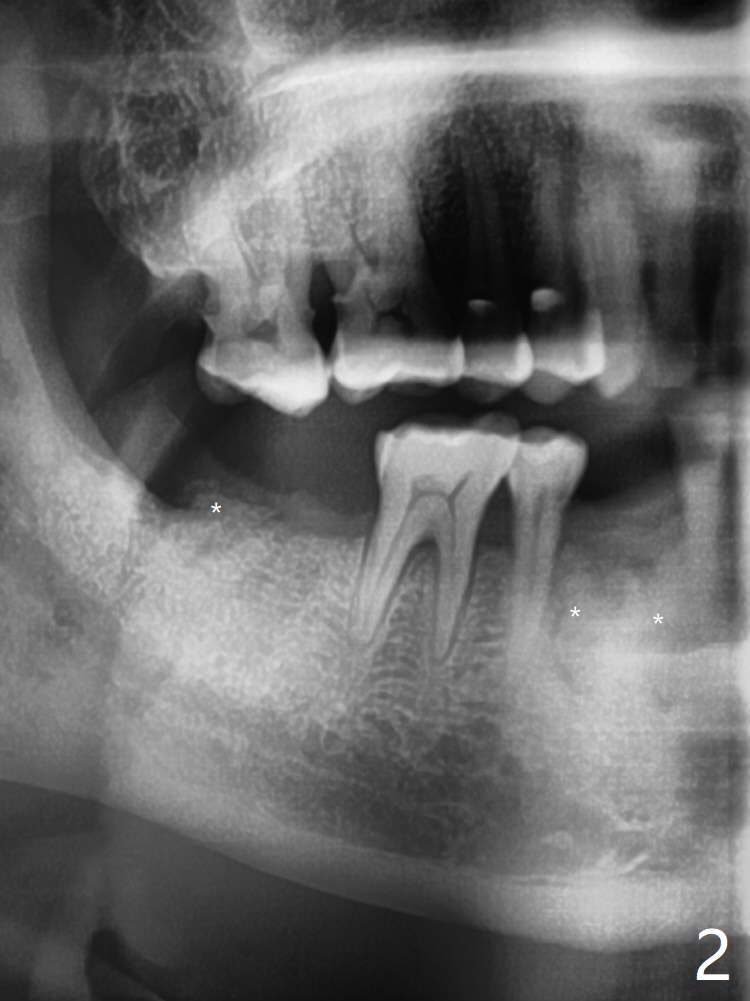

66岁男1.5年前来诊所拍摄全景片(图一),似乎27,28号牙还能保留,今天突然回来,主诉27、28区疼痛瘘道,商量决定先拔除27,28,32及右下深洗。拔除32号牙时发现它接近31区(将要植牙),必须植骨(近中部分(远中塞入胶原塞)),27,28颊侧骨板缺失(大量肉芽组织),植骨理所应当,而且必须拼命推压,但愿推到颊侧骨板,细的皮质骨没有压制感,非要加入粗的松质骨皮质骨,一张12x12毫米胎盘膜剪成两片覆盖27/28和32拔牙窝,4-0 PGA缝线固定,拍摄术后半侧全景片后(图二 (*:骨粉)),使用牙周敷料保护伤口。术后一个月27,28号牙位骨粉保持原位,而且颊侧骨板好像已经重建(图八,十一,九),似乎能植入两个植体(图十,十二)。